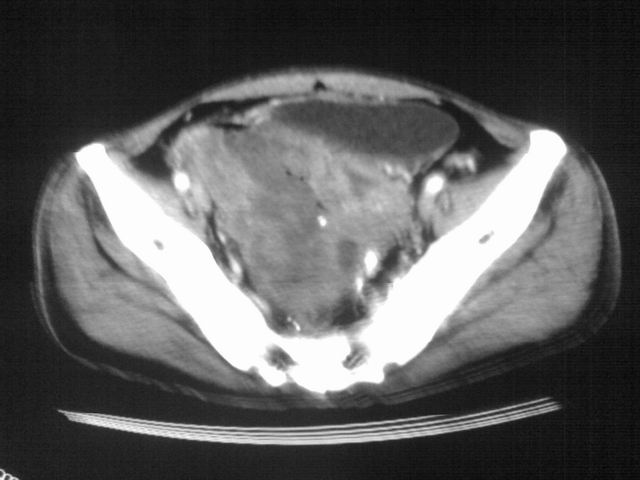

患者m 56岁,盆腔及下腹部胀痛半年,加重1月余,消瘦\中重度贫血.(附:平扫时直肠的高信号为,残留的钡剂).补一下病史:胃镜及纤维结肠镜均无明显异常.

首先是病灶的定位,平扫看很象肠管肿瘤但既然纤维结肠镜正常就可以除外结肠病变,增强成不均匀强化,位于右下腹部应该首先考虑回肠末段占位性病变,1淋巴瘤,2间质瘤,3腹膜后神经原肿瘤待除外,

膀胱后方及直肠前方见巨大混杂密度影,与前列腺相连且向膀胱内突入,精囊腺显示不清;考虑前列腺癌侵犯精囊、膀胱。

膀胱及直肠间有不规侧的软组织密度影,内密度不均匀。其内有坏死囊变,前列腺及精囊腺,膀胱后壁受浸。结合病史考虑腹膜后肉瘤可能性大。